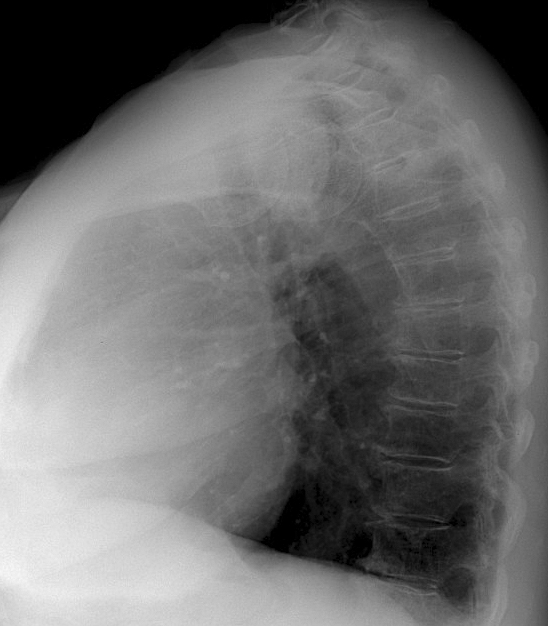

Thyroid Mass

Case 6 Lat